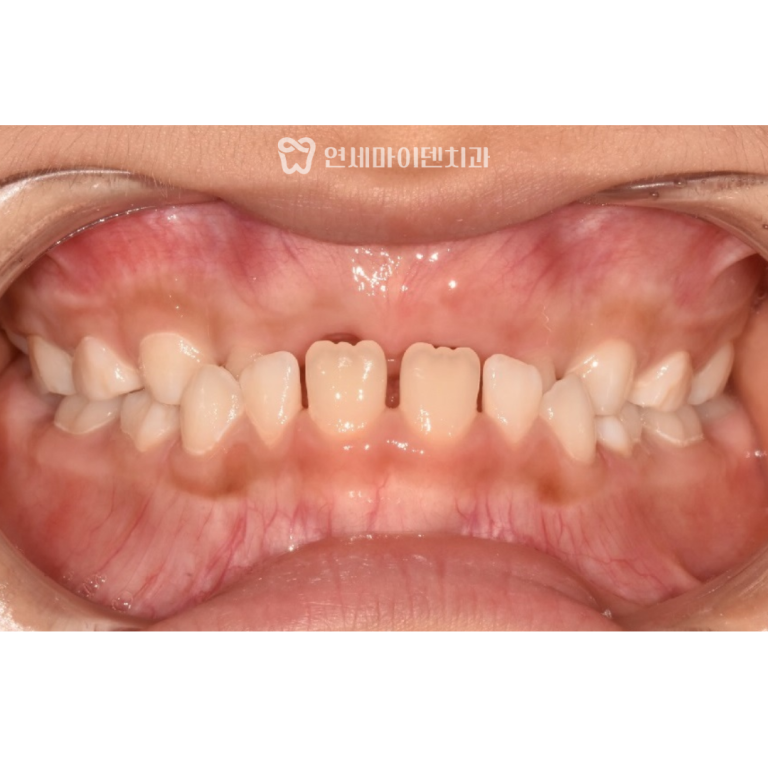

파노라마 방사선 사진을 확인해 보니,

오른쪽 아래 어금니 뿌리 주변의 잇몸뼈가 상당히 녹아 있었습니다.

반대쪽 치아도 이미 발치 후 브릿지로 연결된 상태였고,

잇몸 건강도 좋지 않았습니다.